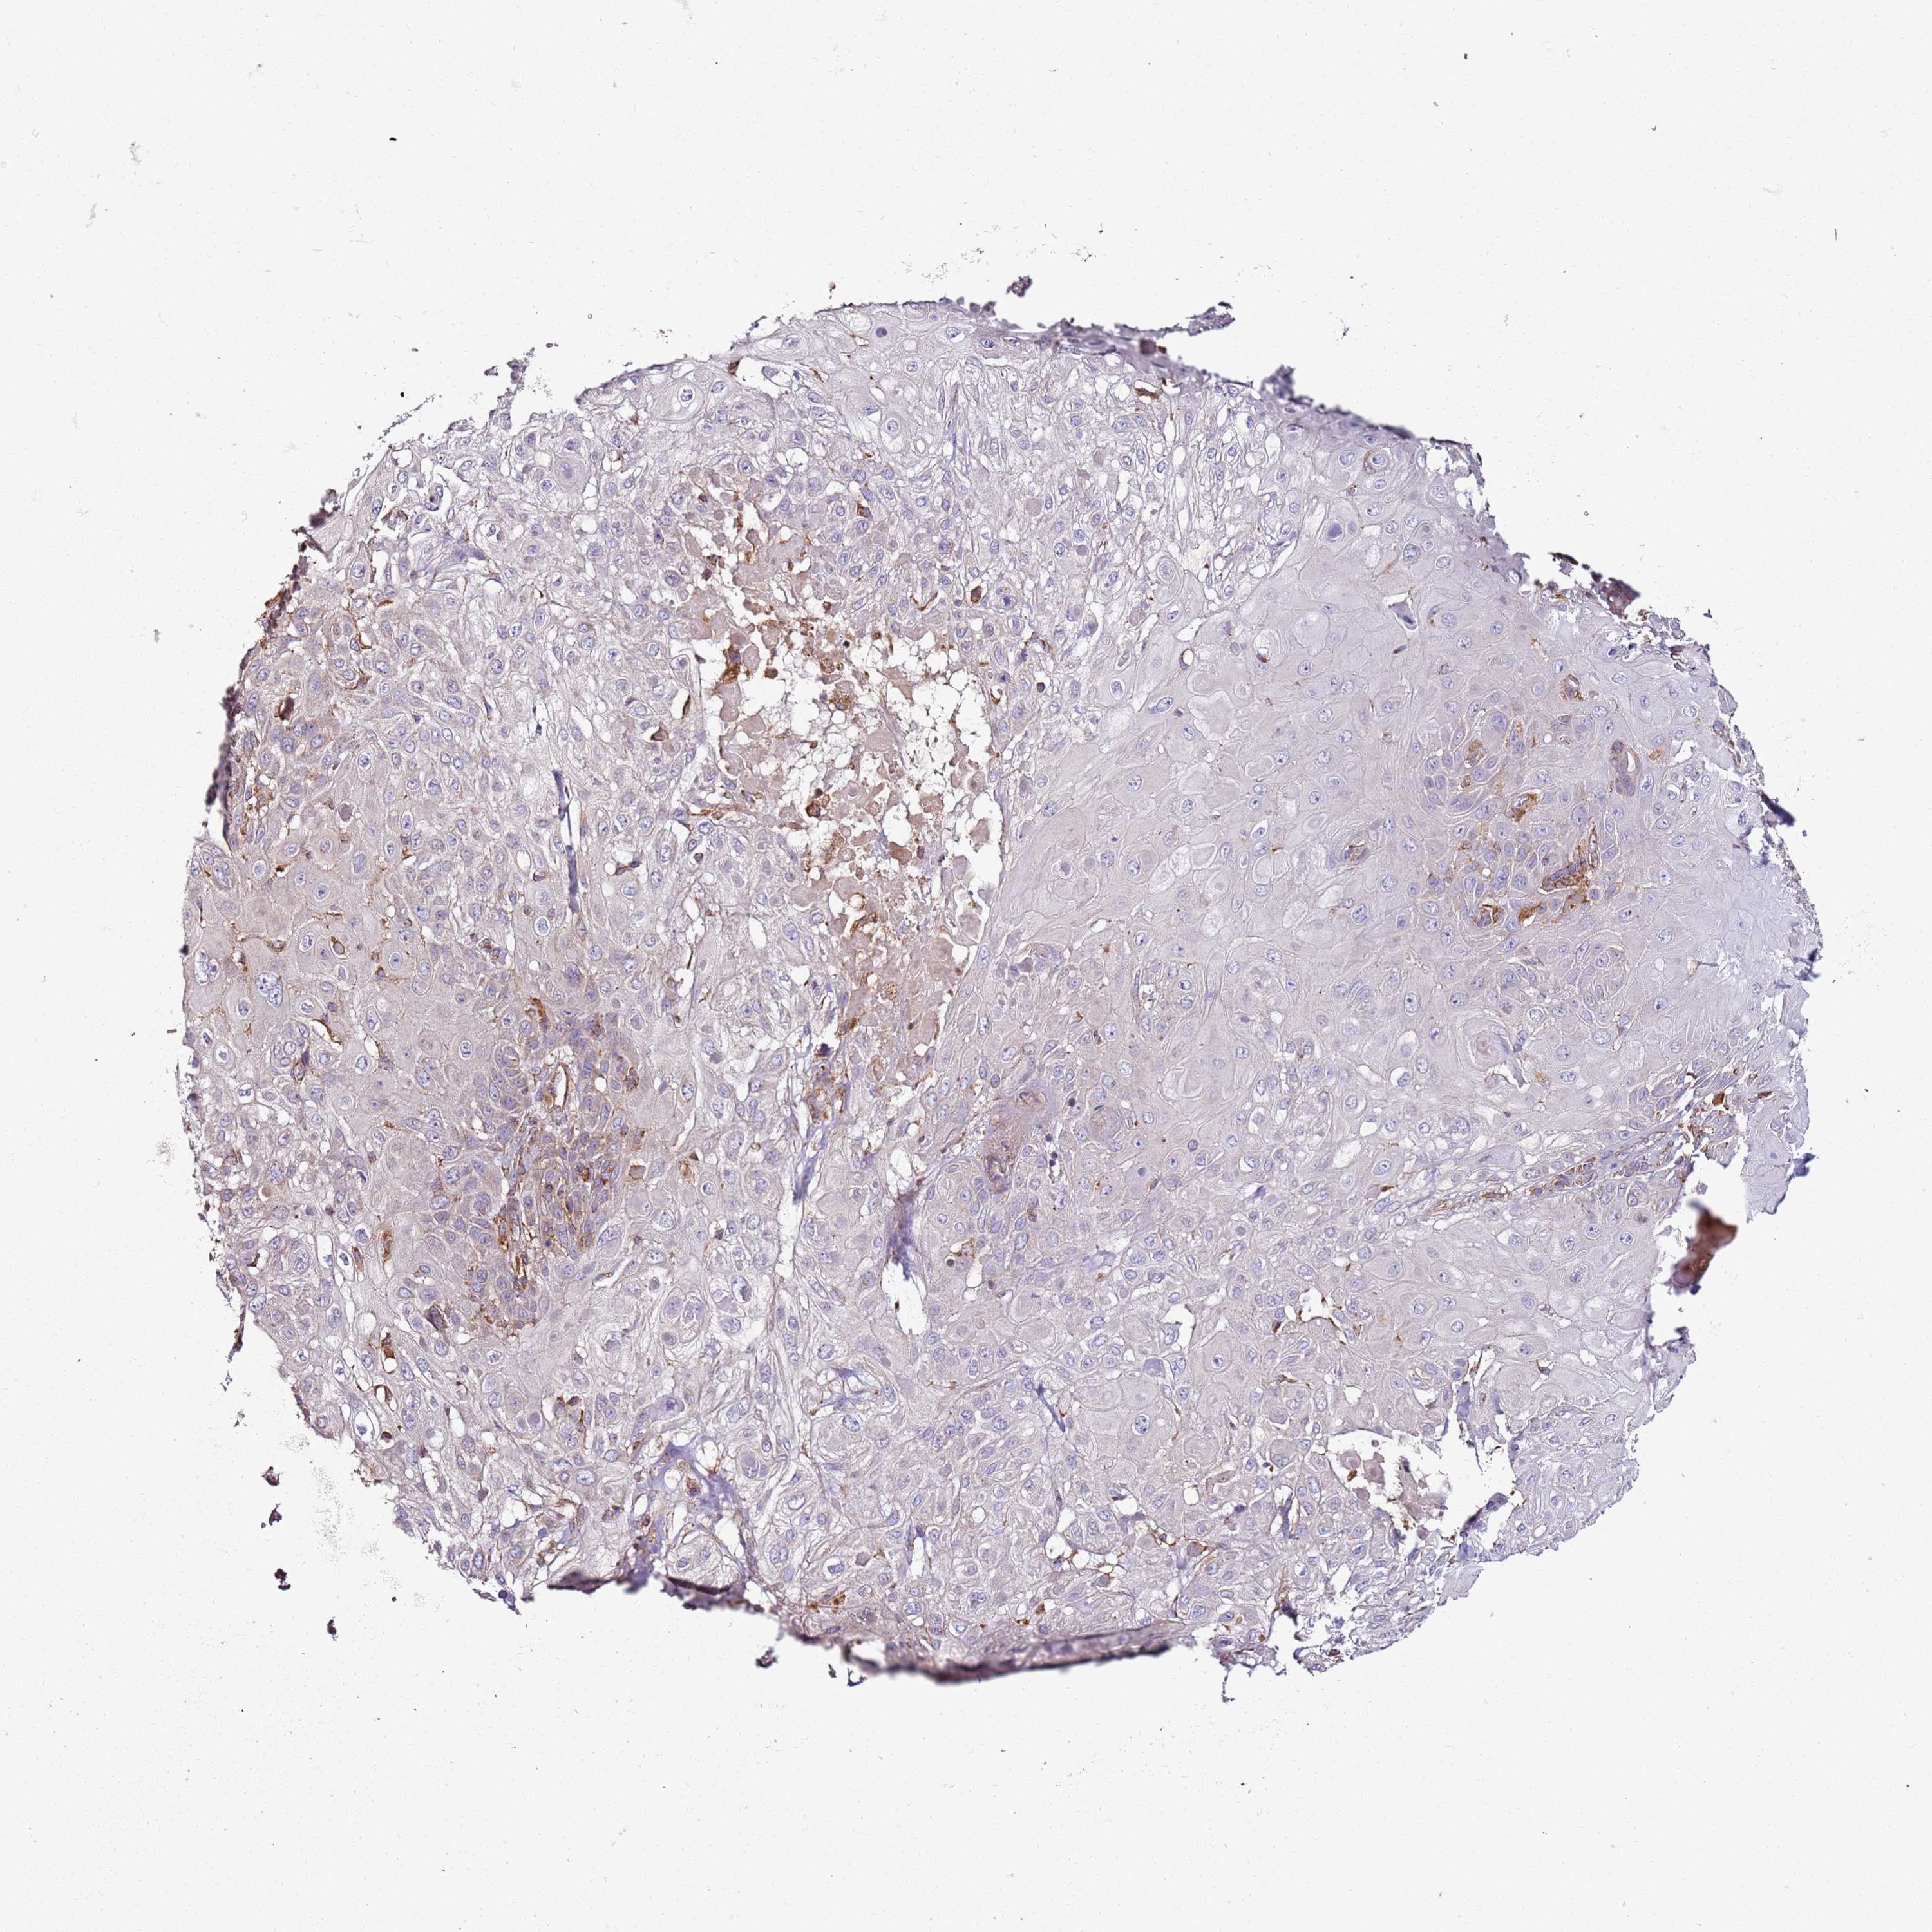

SKIN CANCER - Protein expressioni

A mouse-over function shows sample information and annotation data. Click on an image to view it in a full screen mode. Samples can be filtered based on level of antibody staining by selecting one or several of the following categories: high, medium, low and not detected. The assay and annotation is described here.

Each image is clickable and will lead to virtual microscopy that enables deeper exploration of all samples and also displays staining intensity scores, fraction scores and subcellular localization as well as patient and tissue information for each sample.

Antibody HPA046795

Staining

Medium

Intensity

Weak

Quantity

<25%

Location

Cytoplasmic/membranous

Squamous cell carcinoma, metastatic, NOS

Squamous cell carcinoma in situ, NOS

Squamous cell carcinoma, NOS